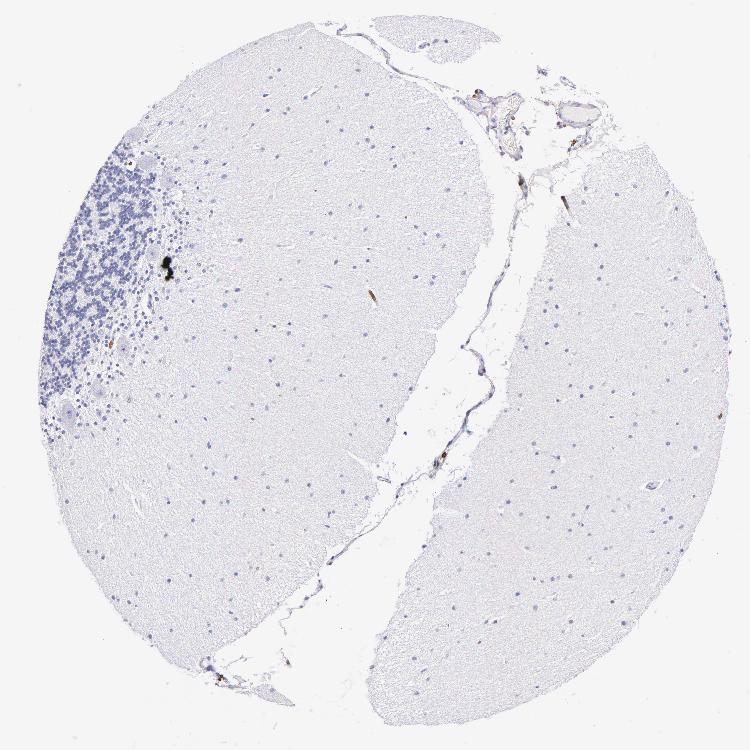

CEREBELLUM - Antibody stainingi

Antibody staining in the annotated cell types in the current human tissue is reported as not detected, low, medium, or high, based on conventional immunohistochemistry profiling in selected tissues. This score is based on the combination of the staining intensity and fraction of stained cells.

Each image is clickable and will lead to virtual microscopy that enables deeper exploration of all samples and also displays staining intensity scores, fraction scores and subcellular localization as well as patient and tissue information for each sample.

Antibody HPA055244Antibody CAB002666

Purkinje cells Not detectedNot detected

Cells in granular layer Not detectedNot detected

Cells in molecular layer Not detectedNot detected